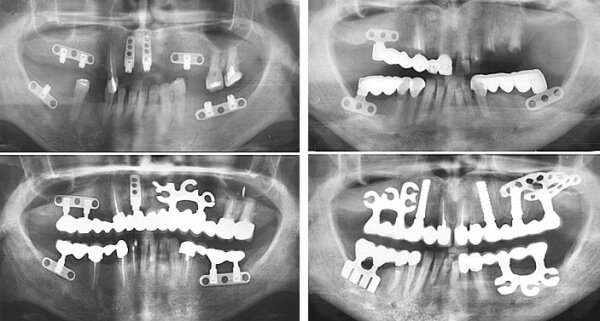

Это не из фантастического фильма)